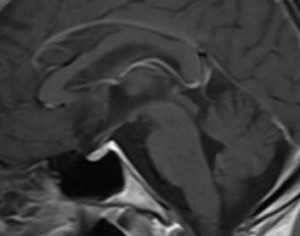

МРТ головного мозга. Сагиттальная Т1-взвешенная МРТ с контрастированием.. Атрофические изменения.

МРТ головного мозга. Т1-взвешенная аксиальая МРТ с контрастированием. Усиление сигнала от сосочковых тел.

МРТ головного мозга позволяет найти типичные признаки энцефалита Вернике - атрофия сосочковых тел, их контрастное усиление на Т1-взвешенных МРТ с контрастированием и общую атрофию мозга. При МРТ головного мозга также описаны высокий сигнал на Т2-взвешенных изображениях от от зрительных бугров, вокруг водопровода